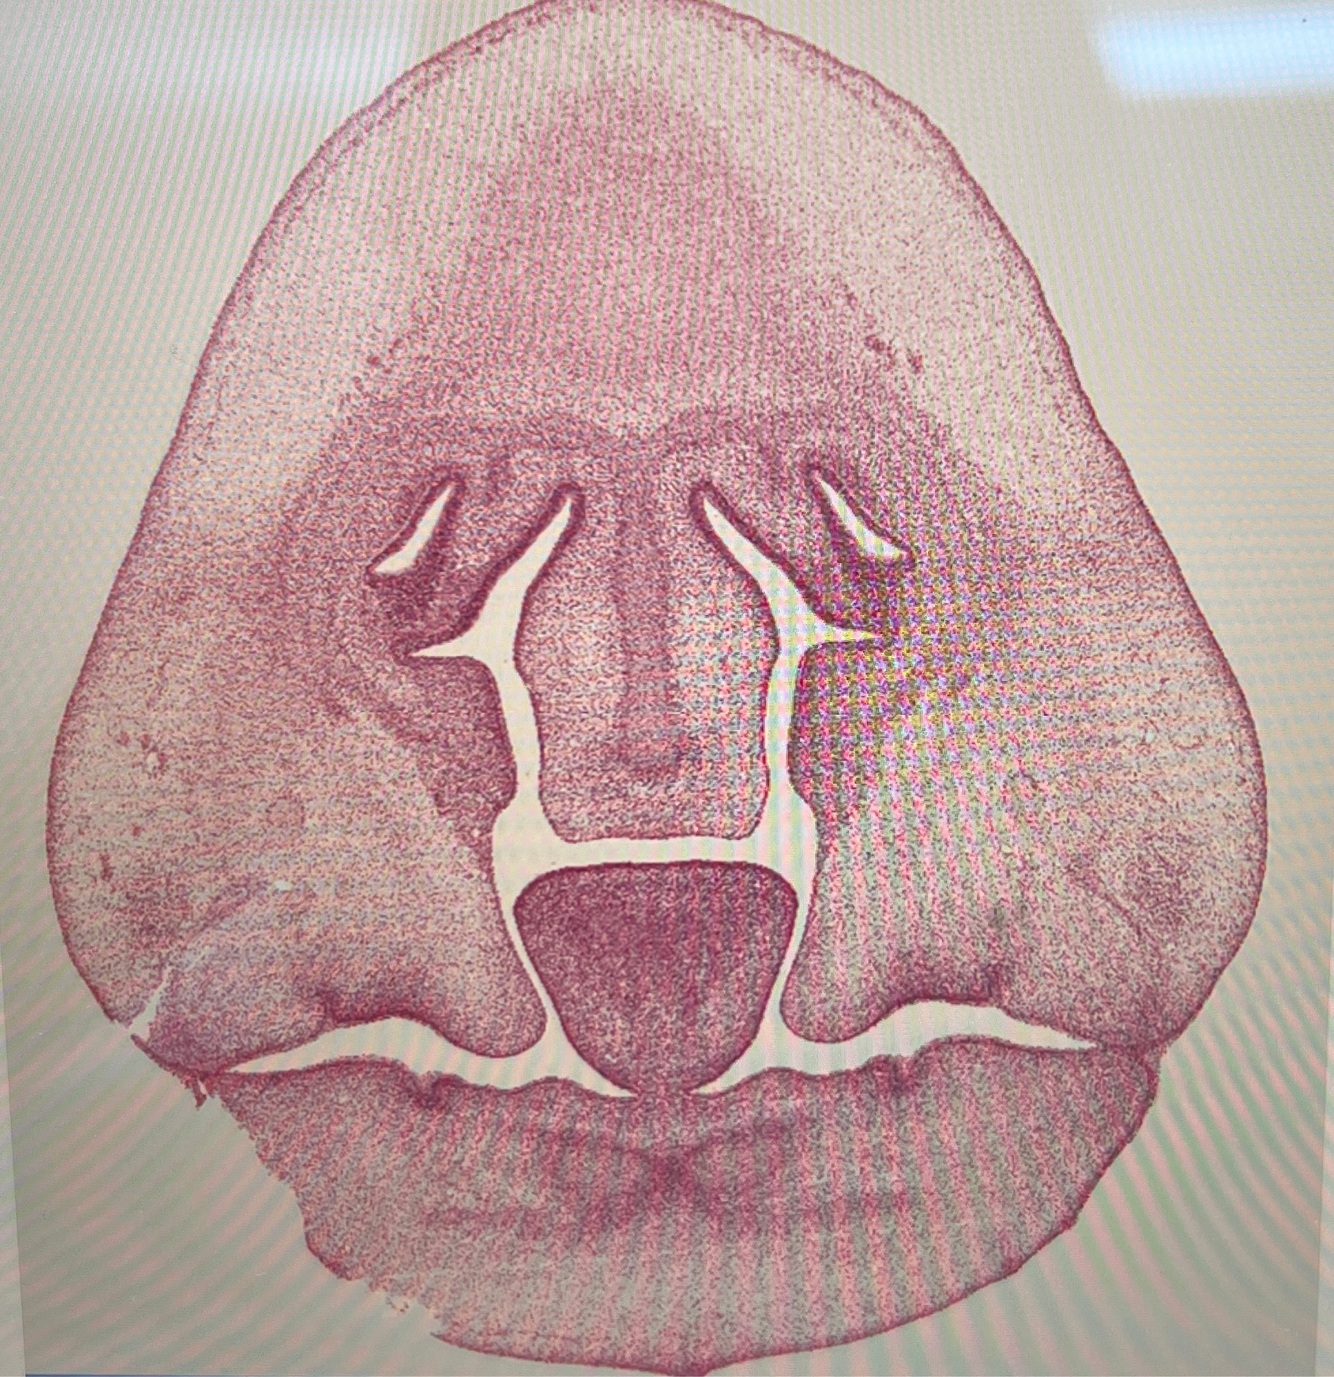

what age is this specimen? why?

Week 8, palatal shelves elevated but not fused yet

palatal shelves